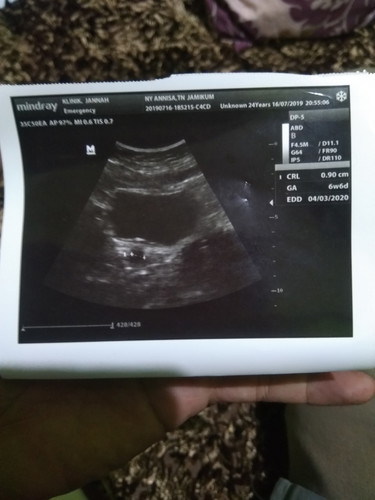

sakit tulang rusuk, dan hasil USG

Minta tolong pak/Bu dokter atau ahli lainnya membaca gambar apakah normal? Terus kemarin sakit punggung, sekarang sakit tulang rusuk, sekarang usia menurut USG 7w1day. Nuhun semuanya???

Itu udah ada janinnya kecil ya